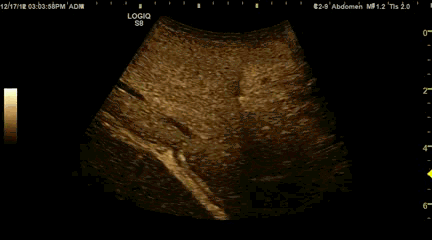

Localizamos la lesión. Son pacientes a quien se le ha detectado en una técnica de imagen anterior un nódulo cuyo aspecto requiere ampliar el estudio, por eso no repetimos la ecografía, solo localizamos la lesión para empezar el estudio.

En la imágenes vemos 5 fases, las dos primeras técnicas donde la imagen sin contraste es medida y estudiada en diferentes potenciaciones en la RMN y en la Eco la estudiamos con y sin doppler.

Después viene la inyección del CIV y sus fases en las dos técnicas donde la lesión realza, se lava y en fase tardía…en fase tardía en la ecografía es donde las lesiones hepáticas nos muestran quien son en realidad.

«Se realiza ecografía abdominal visualizando en el LHD una lesión hipoecogénica de aproximadamente 3 cm. Tras inyección intravenosa de contraste  ultrasonografico se observa una captación temprana de la lesión con un realce muy importante y con una rápida pérdida de  realce siendo la lesión hipoecogénica en la fase tardía. Esto sugiere una lesión con un comportamiento que no es característico de lesión benigna por lo que recomendamos punción aspiración con aguja fina para diagnóstico citológico» Típico informe radiológico…Observa el detalle del comportamiento en fase tardía.